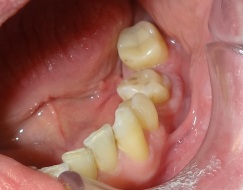

Odbudowa korony zęba trzonowego nakładem kompozytowym. Ząb przeleczono kanałowo i wzmocniono sztyftami z włókna szklanego.